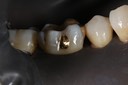

Alan Chinn #31 caries removal